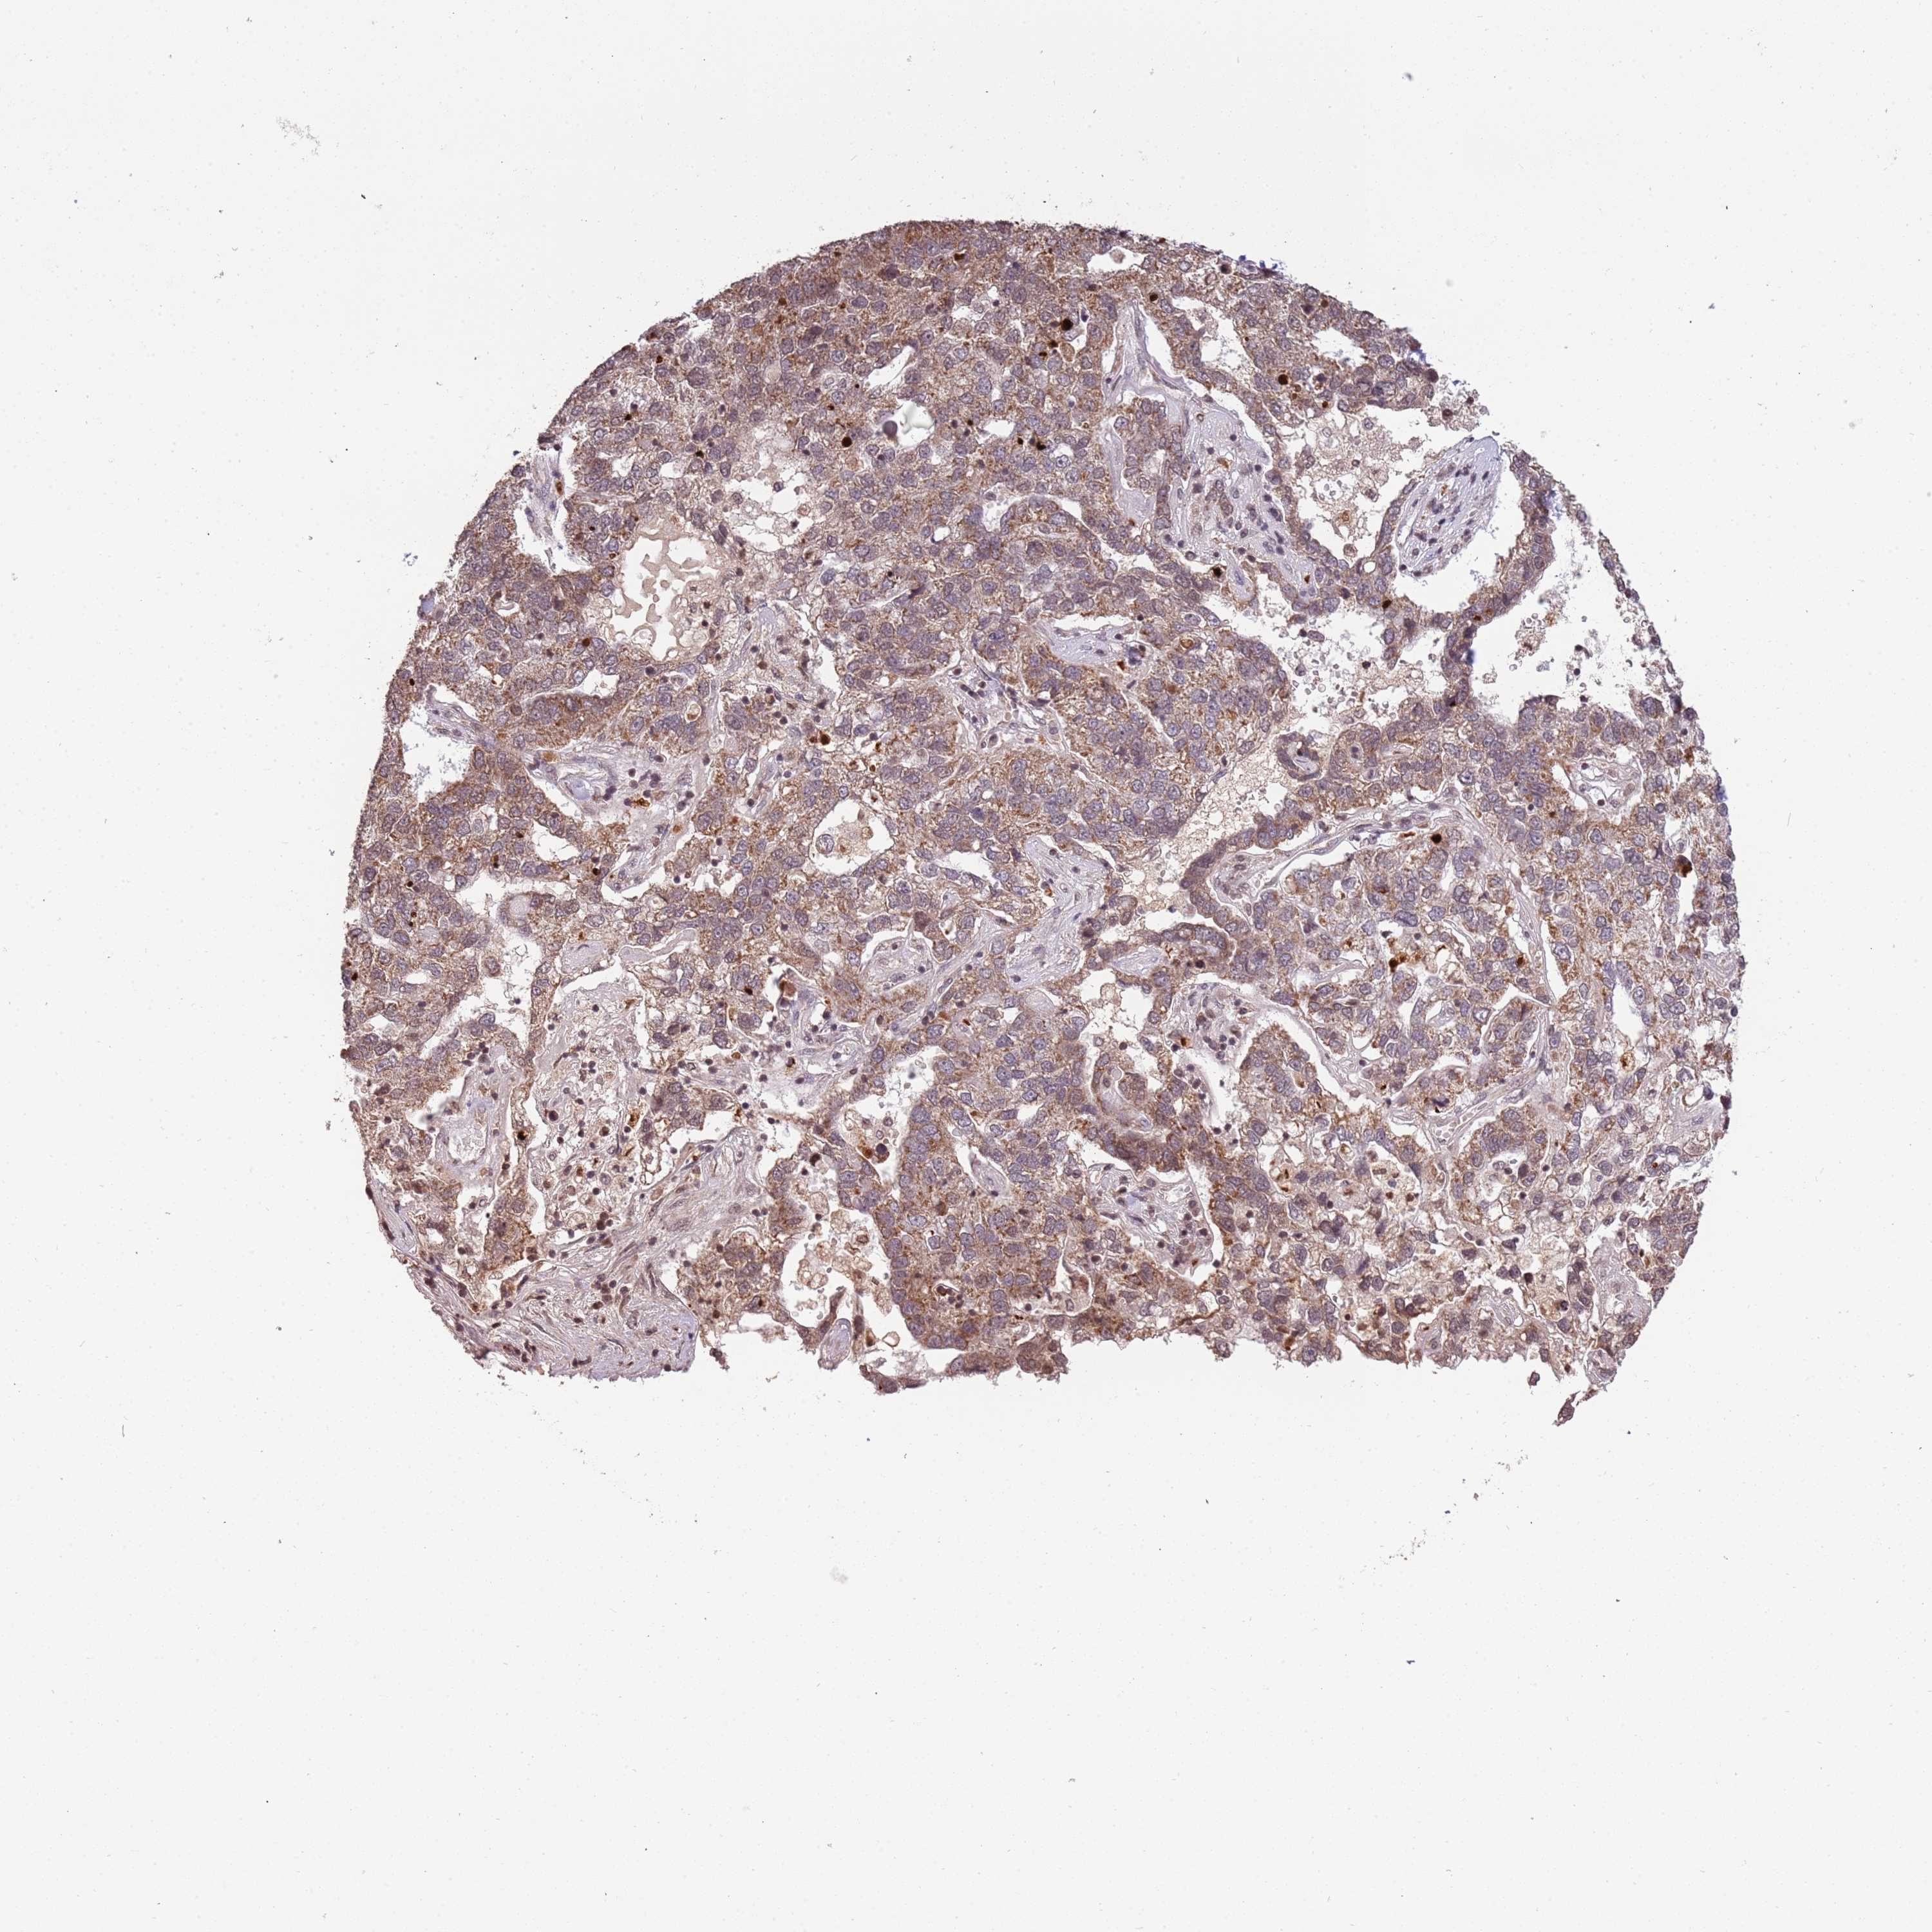

PANCREATIC CANCER - Protein expressioni

A mouse-over function shows sample information and annotation data. Click on an image to view it in a full screen mode. Samples can be filtered based on level of antibody staining by selecting one or several of the following categories: high, medium, low and not detected. The assay and annotation is described here.

Note that samples used for immunohistochemistry by the Human Protein Atlas do not correspond to samples in the TCGA dataset.

Antibody stainingi

Antibody staining in the annotated cell types in the current human tissue is reported as not detected, low, medium, or high, based on conventional immunohistochemistry profiling in selected tissues. This score is based on the combination of the staining intensity and fraction of stained cells.

Each image is clickable and will lead to virtual microscopy that enables deeper exploration of all samples and also displays staining intensity scores, fraction scores and subcellular localization as well as patient and tissue information for each sample.

Antibody HPA010645

Antibody HPA017055

Antibody HPA046639

Staining

High

Medium

Low

Not detected

Intensity

Strong

Moderate

Weak

Negative

Quantity

>75%

75%-25%

<25%

None

Location

Nuclear

Cytoplasmic/membranous

Cytoplasmic/membranous,nuclear

Adenocarcinoma, NOS

Adenocarcinoma, metastatic, NOS